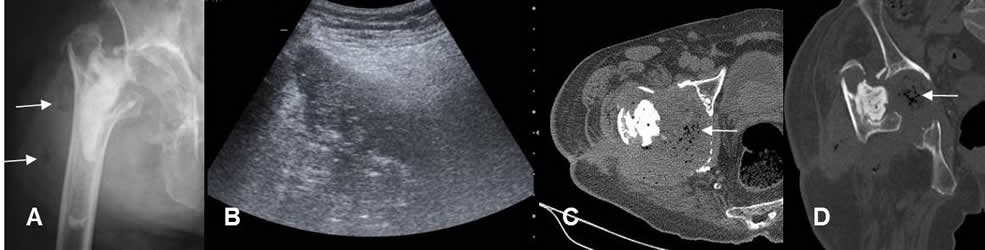

Fig 137. Infección asociada al material.

A: Rx AP. Infección en la prótesis de cabeza femoral, que obligó a su retiro. Hay luxación de la articulación y burbujas de aire en los tejidos blandos.

B: Ecografía. Imagen mal definida en los tejidos blandos, que corresponde a colección.

C: TAC axial y D: TAC reconstrucción coronal. Artritis séptica en la cadera, con abundante líquido y aire sobre la cavidad articular.